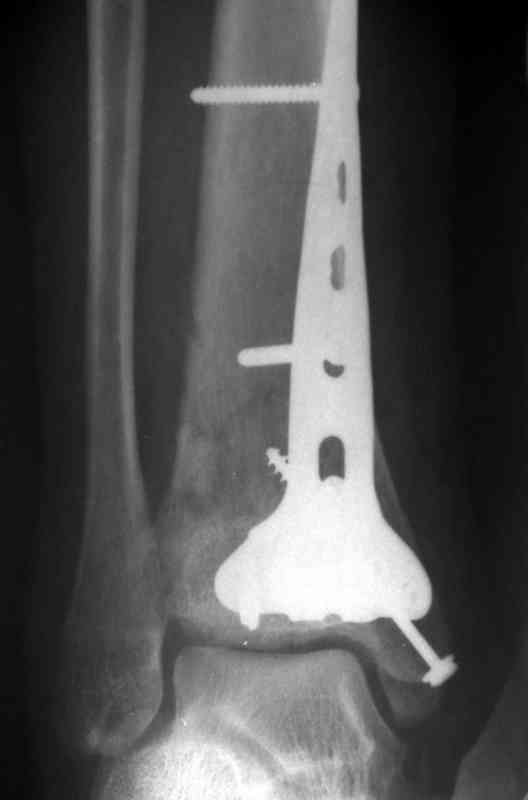

Кстати, при переломах переднего края по классификации АО В-3 при переломах пилона пластина укладывается по передней поверхности. Она достаточно тонкая и эластичная, не надо этого бояться. Посылаю три снимка.